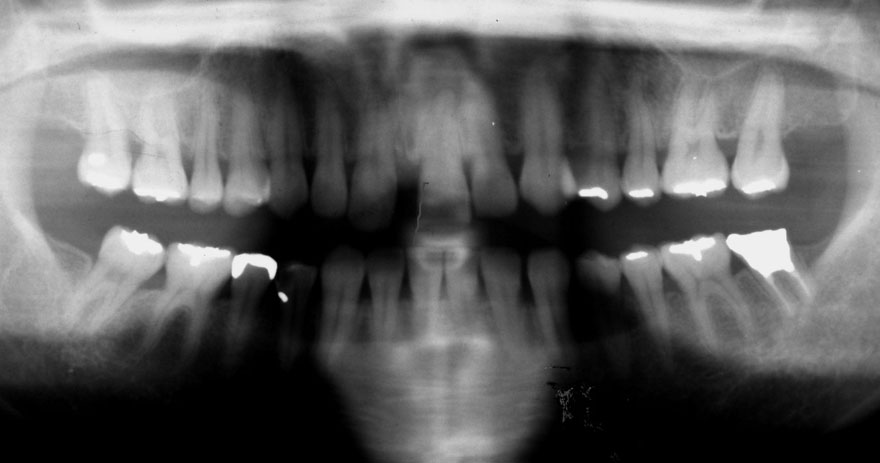

初診時 36歳 女性 平均歯槽骨喪失量:2.70mm

30年後 66歳

平均歯槽骨喪失量:3.26mm

30年間喪失量:-0.55mm

年間喪失速度:-0.018mm

(ケア頻度:3.01ヵ月ごと)